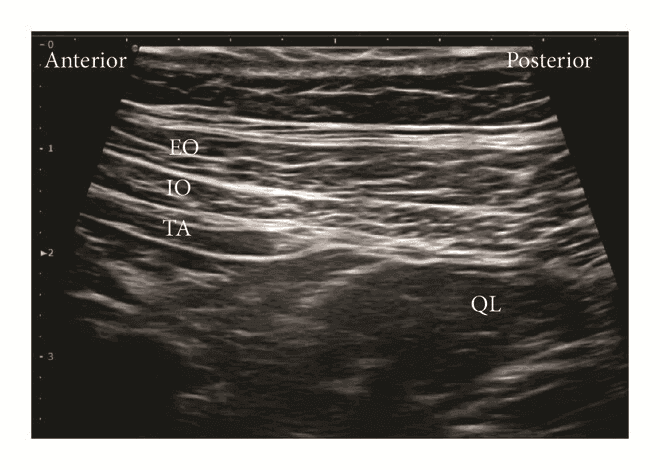

Для блокади QLB тип 1 лінійний датчик розміщують в поперечній площині по середньоаксилярній лінії, і переміщують назад доти, поки m. quadratus lumborum не стане видимим. Голку вводять in-plane з переднього або заднього краю датчика і просувають до моменту, коли вона пройде апоневроз поперечного м’яза живота, і її кінчик досягне простору між латеральною поверхнею m. quadratus lumborum та fascia transversalis. Місцевий анестетик вводять між апоневрозом і fascia transversalis біля латерального краю квадратного м'яза попереку.

Задня QL-блокада (тип 2 QLВ, QLB2)